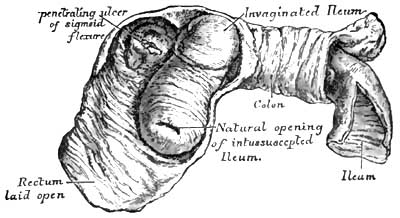

| 26. | SIMPLE INVAGINATION OF THE ILEUM |

| 27. | SIMPLE INVAGINATION, WITH OCCLUSION OF BOWEL, FROM INFLAMMATORY CHANGES |